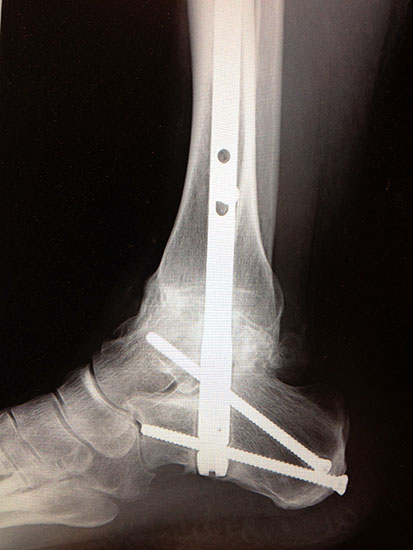

Fixation mit mindestens 2, ggf. 3 kanülierten Schrauben (6,0, 6,5 oder 7,0 mm), die von medial-kranial und lateral-kranial nach kaudal oder von anterior-kranial nach posterior-distal (Abb. 6) in den Talus unter BV-Kontrolle in 2 Ebenen eingebracht werden (Sabo 2014). Im amerikanischen Sprachraum ist die Verwendung der von dorsal-lateral paraachillär nach anterior-medial in den Corpus tali gerichteten Zugschraube geläufig („home run-screw“) (Abb. 7). Es ist darauf zu achten, das untere Sprunggelenk nicht mit Schrauben zu perforieren. Idealerweise spannen die Kompressionsschrauben, deren Gewindegänge nur im Talus liegen sollten diesen stabil in die Malleolengabel ein.

Abbildung 6